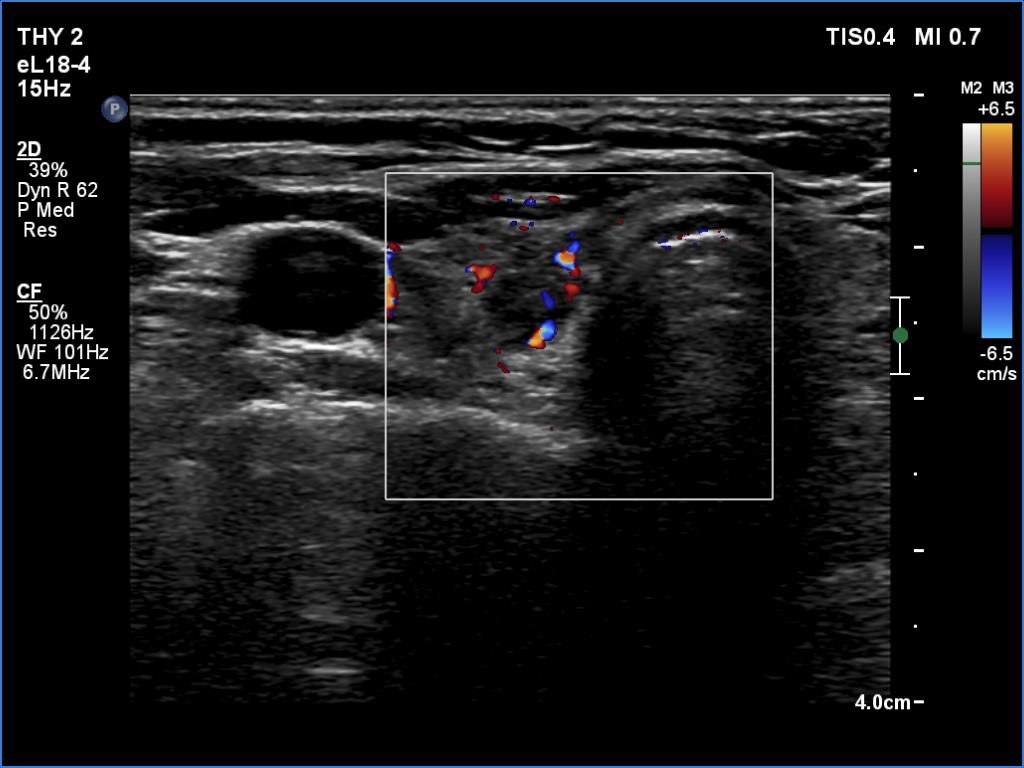

Ultrasonography. The thyroid was atrophic and hypoechoic. There was a hypoechoic mass under the lower pole of the left lobe.